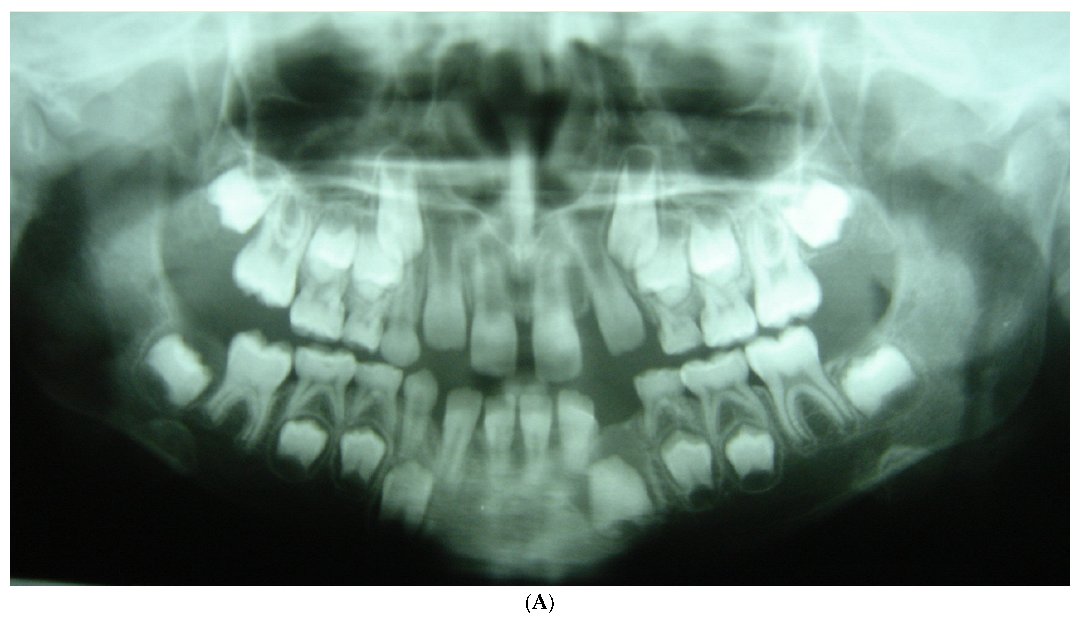

| Chinese-Americans | 151 | 73 | 78 | 90 | 61 | 212 |